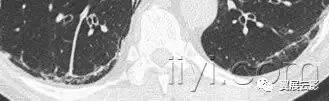

十一、支气管扩张

病理:是不可逆性的局限或弥漫性支气管扩张,通常是慢性感染、近端气道梗阻或者先天性支气管异常造成的。

平片和CT:薄层CT上的形态学标准为:与临近的血管相比,支气管扩张呈印戒征,支气管逐渐变细的形态消失。胸膜下25px内可见气管分支。根据受累气管的形状,支气管扩张可以分为管状、蔓状或囊状。经常伴随关闭的增厚、粘液嵌塞和小气道的异常。